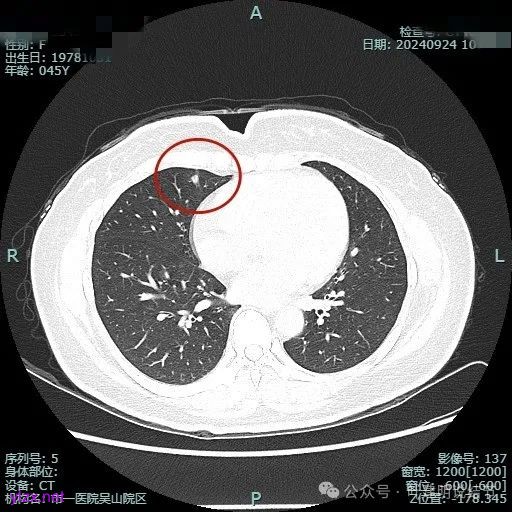

病灶2:

右中叶内侧段可见混合密度结节,大部分实性,形态与下叶背段的类似。